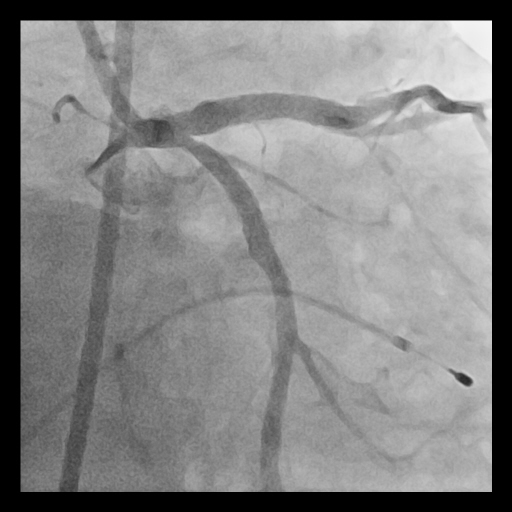

Given the extensive and concentric calcium across the LM bifurcation, an upfront ¡°Rotatripsy¡± strategy (rotational atherectomy followed by intravascular lithotripsy) was selected. A 1.25 mm burr was used for initial channel creation in the LCx and LM-LAD, with transient bradycardia requiring temporary pacing. Post-rotablation IVUS revealed residual deep calcium. Subsequently, intravascular lithotripsy (IVL) using a 3.5–4.0 mm balloon (1:1 sizing to proximal LCx and LM) was applied with 8 cycles, achieving clear calcium fracture on IVUS. Two DES were implanted sequentially (LCx: 3.5¡¿28 mm; LM–LAD: 4.0¡¿38 mm), followed by high-pressure post-dilation and final kissing balloon inflation. Final IVUS confirmed optimal stent expansion (MSA: LCx 7.7 mm©÷, LAD 12.1 mm©÷, LM 13.2 mm©÷) and well-apposed stents throughout the bifurcation.

Case Summary

Upfront Rotatripsy combining rotational atherectomy and intravascular lithotripsy can effectively manage severely calcified LM bifurcation lesions. Intracoronary imaging is essential for understanding calcium morphology and guiding appropriate modification strategy. The hybrid approach ensures both superficial debulking and deep calcium fracture, achieving predictable stent expansion and durable results.